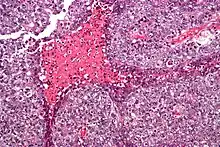

Micrograph of an embryonal carcinoma showing its typical features – prominent nucleoli, marked nuclear atypia, necrosis, and nuclear overlap. H&E stain.

The microscopic features include: indistinct cell borders, mitoses, a variable architecture (tubulopapillary, glandular, solid, embryoid bodies – ball of cells surrounded by empty space on three sides), nuclear overlap, and necrosis.